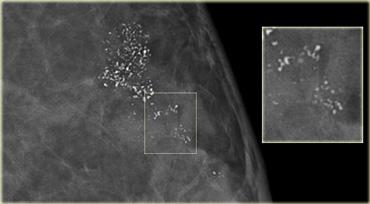

Các vôi hóa ở hình bên trái được phát hiện trên lần chụp nhũ ảnh đầu tiên trong chương trình tầm soát.

Có một cụm vôi hóa vô định hình và đa hình thái mịn.

Các vôi hóa này được phân loại là BI-RADS 4B.

Sinh thiết được thực hiện và chỉ phát hiện các thay đổi xơ nang.

Hình bên trái là một trường hợp trông khá tương tự với trường hợp trên.

Các vôi hóa mới được phát hiện trong quá trình theo dõi thuộc chương trình tầm soát.

Đây là các vôi hóa đa hình thái mịn tập trung thành cụm.

Các vôi hóa này được phân loại là Bi-RADS 4.

Kết quả xác nhận là DCIS.

Thông điệp rút ra là với các vôi hóa dạng này, không thể xác định được chúng là ác tính hay không và bắt buộc phải tiến hành sinh thiết.